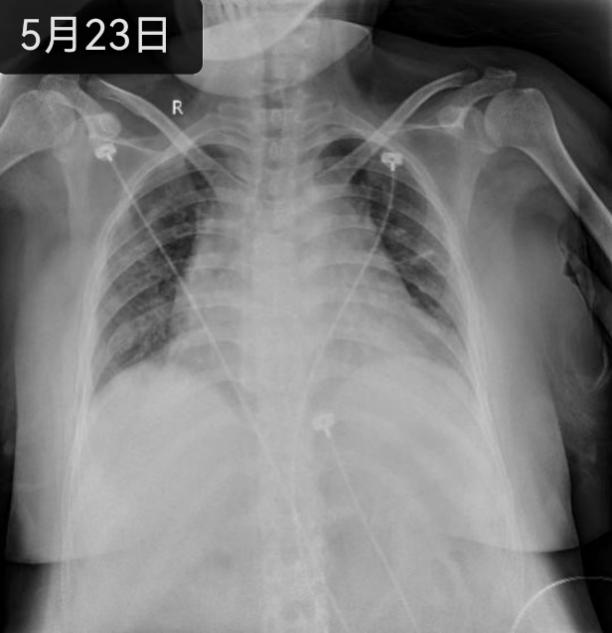

综合判断病情后,方萍教授当机立断,迅速联和急诊ECMO团队启动VV-ECMO治疗,刘丽萍副护士长立即召集ECMO护理小组成员放弃休假归队。医护争分夺秒,默契配合,只为与死神赛跑。当暗红色血液经过“膜肺”氧合后变成鲜红色,源源不断重返患者体内,患者生命体征逐渐平稳,ECMO的建立为心肺功能恢复赢得了时间。随后,RICU医护团队通过床旁气管镜、床旁超声、一氧化氮吸入、EIT、无创、有创血流动力学监测等技术实时精准评估和管理患者,制定了包括ECMO管理、呼吸支持、气道保护、容量管理、出凝血管理、感染与免疫、院感防控、镇痛镇静、营养支持和呼吸康复在内的一系列个体化精准诊疗方案,同时组织了包括呼吸、风湿免疫、急诊、重症、检验、药学等相关科室的数次MDT。经过14天ECMO支持、21天气管插管有创机械通气以及针对原发病的积极救治,患者最终转危为安,于入院后第27天顺利转回当地医院康复治疗。